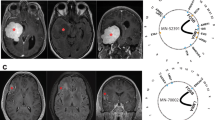

RNA-Seq and validation for gene fusions. (A) Dendrogram for clustering RNA-Seq data. Malignant and benign meningiomas were labelled with M and B, respectively. (B) Gene fusions of NAB2-STAT6 and STAT6-NAB2 validated by RT–PCR and Sanger sequencing. The translated amino-acid sequences at the in-frame fusion junctions are also shown. (C) Gel electrophoresis of the amplified products.

Abnormal gene fusion events have been identified in a series of tumour types (Nowell, 1962; Tomlins et al, 2005; Chmielecki et al, 2013; Robinson et al, 2013). From RNA-Seq data, two gene fusions (NAB2-STAT6 and STAT6-NAB2) were identified in the malignant sample 255. Interestingly, gene fusions of NAB2-STAT6 have been reported in recurrent SFTs, including higher-grade tumours, which in the past were considered a separate entity called hemangiopericytoma (HPC; Chmielecki et al, 2013; Robinson et al, 2013). Sample 255 had an unusual histological appearance and immunophenotype with features of both meningioma and HPC (see Discussion below). The fusion of NAB2-STAT6 in our study is localised between the end of exon 6 of NAB2 and the beginning of exon 18 of STAT6, with 98 junction reads identified from RNA-Seq data (Supplementary Table 2). The fusion of STAT6-NAB2 was supported by 126 junction reads, which connects the last nucleotide of exon 17 of STAT6 with the first nucleotide of exon 7 of NAB2. In other meningioma samples, these two gene fusions were not detected from RNA-Seq data (in the malignant sample 010, one junction read was detected and was likely due to noise). Interestingly, the normally spliced junctions between exon 6 and exon 7 of NAB2 as well as between exon 17 and exon 18 of STAT6 were also detected in sample 255, supported by 99 and 57 junction reads, respectively. Thus, the gene fusions could result from genomic alteration in one of the two alleles or a subset of the tumour cells. The gene fusion detected by RNA-Seq technique was subsequently validated using RT–PCR and Sanger sequencing. Consistent with RNA-Seq data, the gene fusions of NAB2-STAT6 and STAT6-NAB2 were only detected in sample 255 by RT–PCR using junction spanning primers (Supplementary Table 3). Sanger sequencing (Figure 2) validated the breakpoints of mRNA fusions detected in next-generation sequencing data. As noted, the exons of NAB2 and STAT6 formed in-frame fusion products. Therefore, the gene fusions occurring at the mRNA level may have resulted in novel protein products.

Both NAB2 and STAT6 are located on 12q13.3 (Figure 3) and are transcribed in opposite directions. Gene fusions of NAB2-STAT6 and STAT6-NAB2 imply potential chromosomal inversion around the q13.3 locus. Based on the gene fusion junctions identified, we hypothesise that chromosomal inversion should cover the genomic regions of exon 7 of NAB2 as well as exons 18 to 23 of STAT6. Another two sets of primer pairs (Figure 3, Supplementary Table 4) were designed to detect chromosomal inversion junctions from PCR amplification of the genomic DNA. Of all seven meningioma samples used for RNA-Seq analysis, the chromosomal inversion junctions were only detected in sample 255. Additional Sanger sequencing of PCR products pinpointed the break-points at the non-coding regions of the genome.